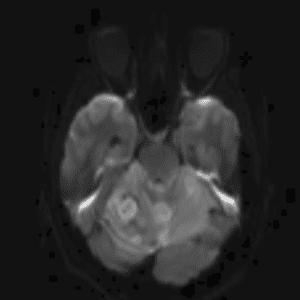

Case #14

CNS toxoplasmosis